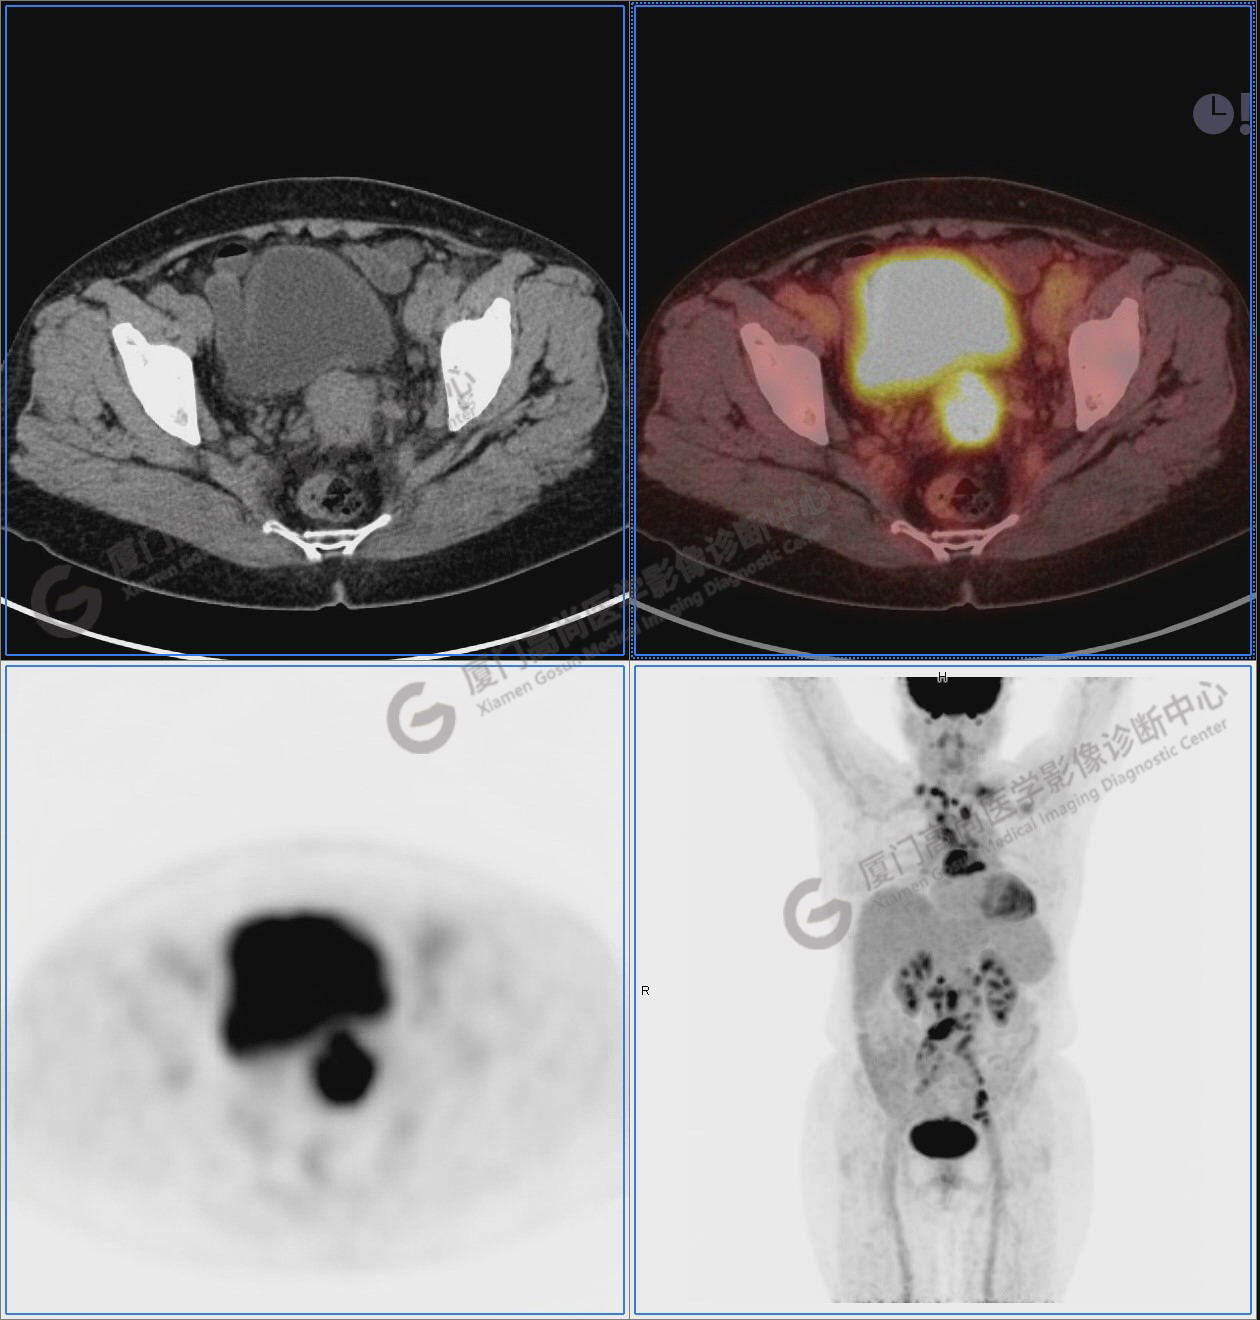

圖10-11:子宮頸軟組織腫塊,代謝異常增高,考慮為宮頸癌。

圖10

圖12-13:延遲2小時后,宮頸腫塊糖代謝進一步增高。